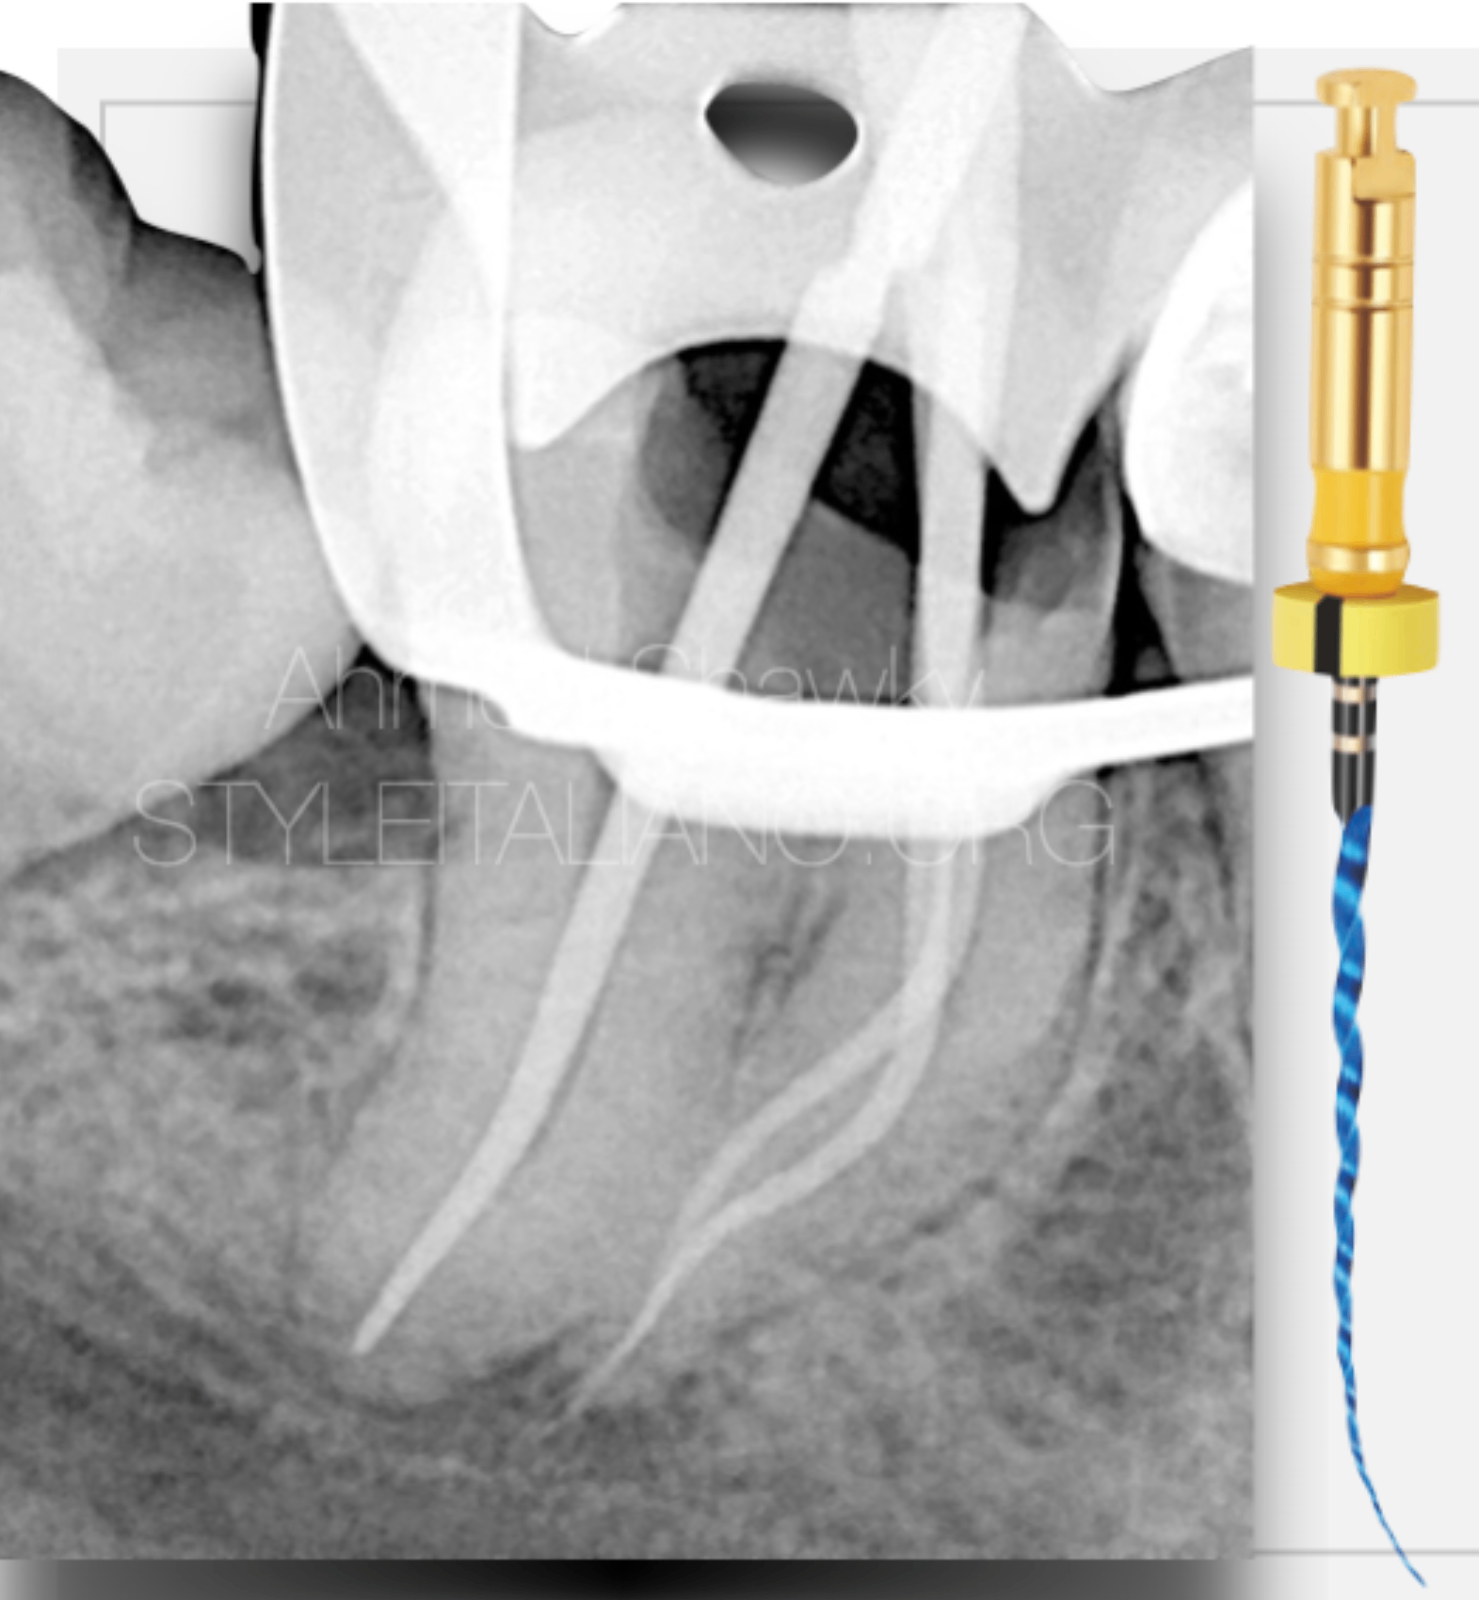

The MG3 Blue instruments, were used in the Body portion and for apical finishing, to benefit from the controlled memory behavior avoiding alteration of the anatomy “transportation”.

Another benefit from using MG3 Blue is the enhanced cyclic fatigue resistance owing to the predominantly martensitic micro-structure

These instruments were used in interrupted rotation [REC mode] with a net clockwise motion (CW 170 / CCW 50)

The Final Shaping size in the mesial root canals were MG3 Blue #20/.04

The Distal root canal was shaped using a single file in interrupted rotation [MG3 Gold, 30/.04]

The irrigation protocol involved full strength NaOCl throughout instrumentation along with continuous chelation using 17% EDTA solution

The final rinse protocol involved activation of both solutions using Ultrasound

Obturation was performed utilizing Warm compaction of gutta percha and heat compatible calcium silicate based sealer